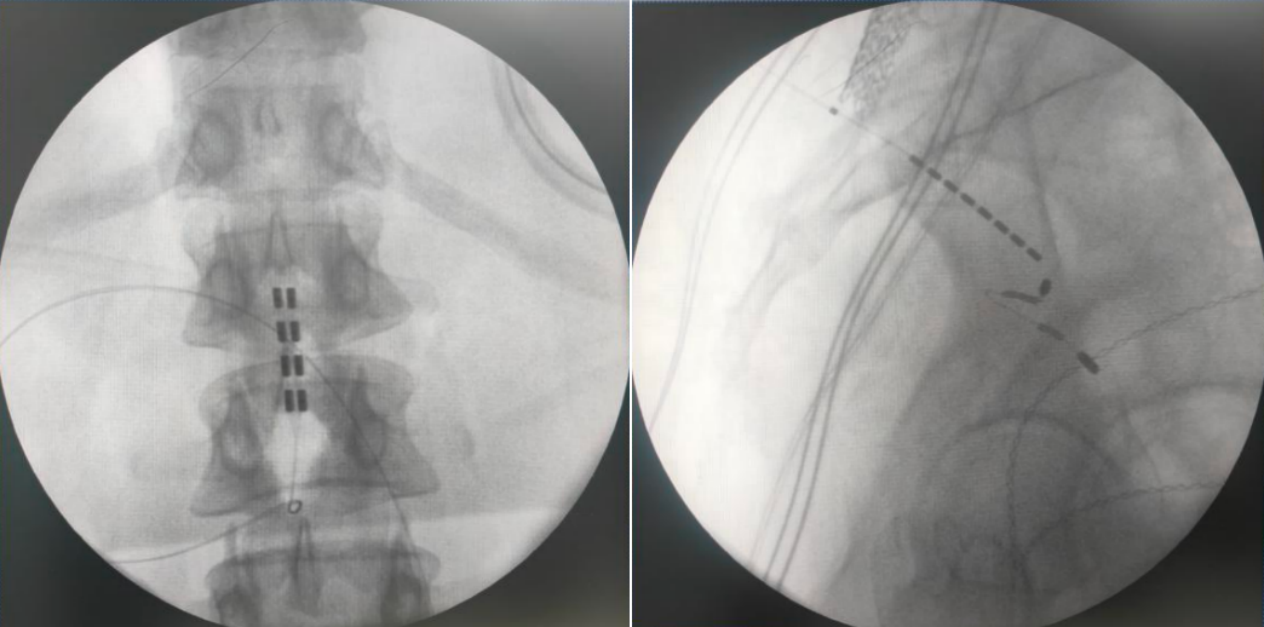

由于该患者为脊髓拴系,脊髓位置偏低,而且脊柱裂合并骶椎骨性解剖畸形给骶孔穿刺带来了非常大的难度,但是通过术前的系统评估以及术中电生理监测,李萃萃主任团队将一根穿刺电极精准置入S3骶孔位置以改善二便功能,另一根4-4排布的片状电极覆盖L1-2节段(患者脊髓低位,放置位置需根据患者情况个性化调整)以调控下肢肌张力异常和感觉障碍。术中测试显示,骶神经刺激可有效引发二便感知,脊髓电刺激则完整覆盖臀部及双下肢。